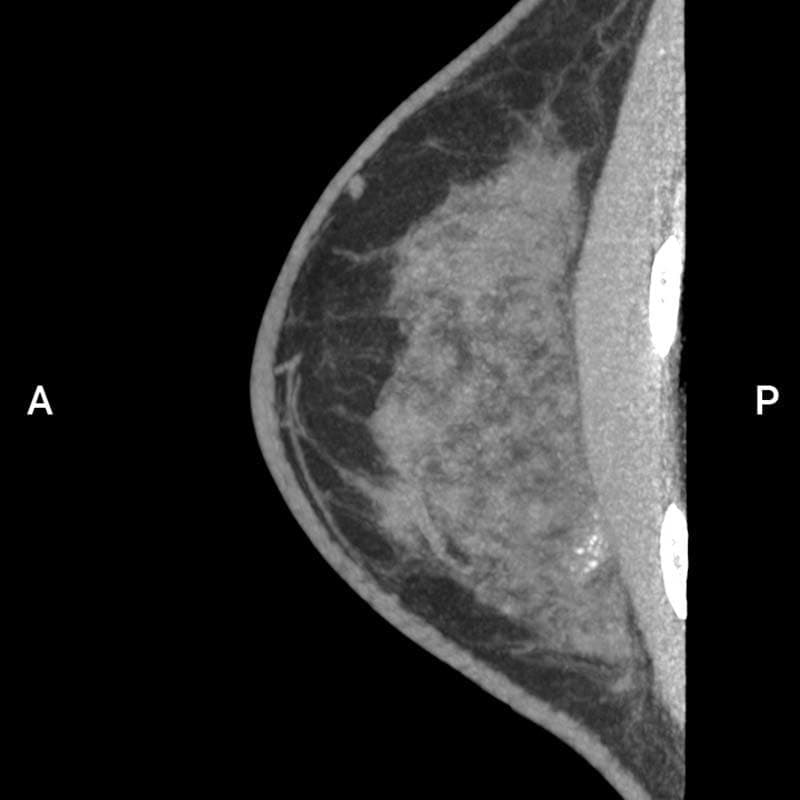

多発性乳がん

患者背景

• 70~79歳の女性で、右乳房に触知可能な腫瘤を認める。

• 過去のマンモグラフィでは単一の腫瘤のみが描出されていた。

• 超音波検査では、病変は円形かつ境界明瞭で、嚢胞性と固形成分を伴っていた。さらに、滑らかで不規則な辺縁を有する複数の低エコー性病変が検出された。

多発性乳がんの疑いを確認するため、乳腺CT検査を実施した。

画像詳細

• 造影前:円形の腫瘤性病変で、中心部に低吸収(壊死/液体)領域を認める。画像所見は複数の病変を疑わせる。

• 造影後:触知可能な腫瘤は造影剤を不均一に増強します。乳房の複数の象限に、不規則な縁と滑らかな縁を有する複数の造影増強腫瘤が明示されています。

評価:BI-RADS 5

画像提供:エヴリン・ヴェンケル医学博士(エルランゲン大学病院)